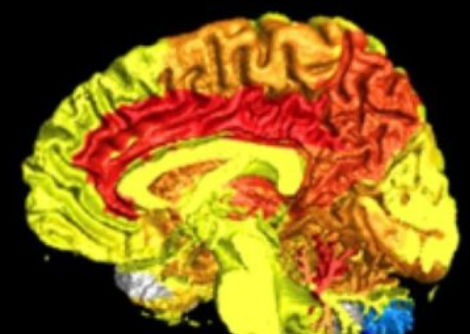

وجد الباحثون زيادة في الخلايا التائية في الكلى والتي تلعب دورًا رئيسيا في تنظيم ضغط الدم. تشجع هذه الخلايا الالتهاب عند كلا الجنسين ولكن كانت الزيادة الأكبر عند الذكور.